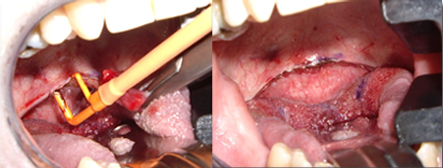

適用于細(xì)微、精細(xì)的切割如頭頸部,敏感部位皮膚的切割。

更佳的美容效果,更快的傷口愈合過程。